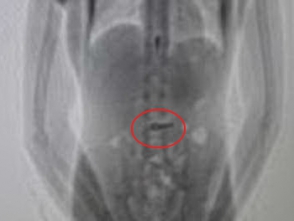

Ուշագրավ դեպք է տեղի ունեցել Ուրուգվայում: Մենդես ազգանվամբ դատապարտյալը, գաղտնի փորձելով ձեռնաշղթաների բանալին իր հետ բանտ անցկացնել, կուլ է տվել այն։ Փորձը, սակայն, չի հաջողվել. բանտի մուտքի մոտ տեղադրված հատուկ սարքերի օգնությամբ ստամոքսում գտնվող բանալին հայտնաբերվել է: Մենդեսը հրաժարվում է այդ միջադեպի վերաբերյալ որևէ ցուցմունք տալ, այդ իսկ պատճառով առայժմ չի հաջողվում պարզել, թե ինչ նպատակով էր բանտարկյալը կուլ տվել բանալին։